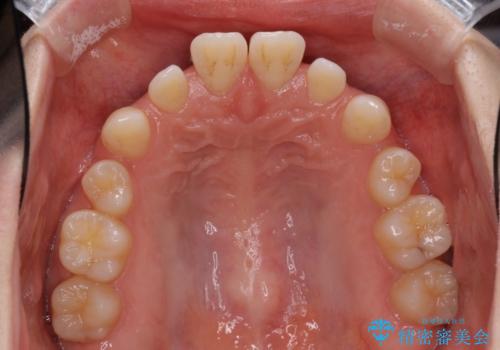

- 歯の欠損による隙間だらけの歯並びを気にして来院された患者様です。

上顎左右1本ずつ欠損していたため、歯列矯正により欠損部位にスペースを集め、その後欠損部位をインプラントにて補綴することとしました。

インビザラインによる矯正治療も提案しましたが、長時間の装着や自己管理が難しいとお考えで、ワイヤーによる矯正治療を行いました。

歯並びは比較的早めに整いましたが、インプラントを埋入するにあたって前後の歯根位置を改善する必要があり、矯正治療に期間を要することとなりました。